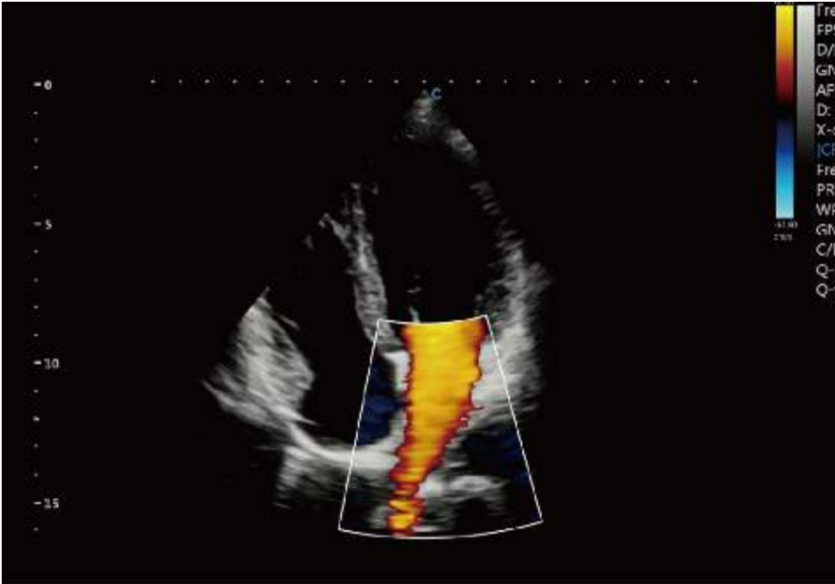

TV Regurgition, CW Mode